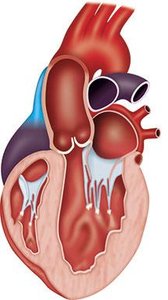

Hypertrophic cardiomyopathy is a genetic disorder characterized by abnormal thickening of the ventricular walls, most commonly the interventricular septum, leading to impaired diastolic filling and sometimes outflow tract obstruction.

Diagnosis: Echocardiography shows asymmetric septal hypertrophy, small left ventricular cavity, and possible outflow tract obstruction.